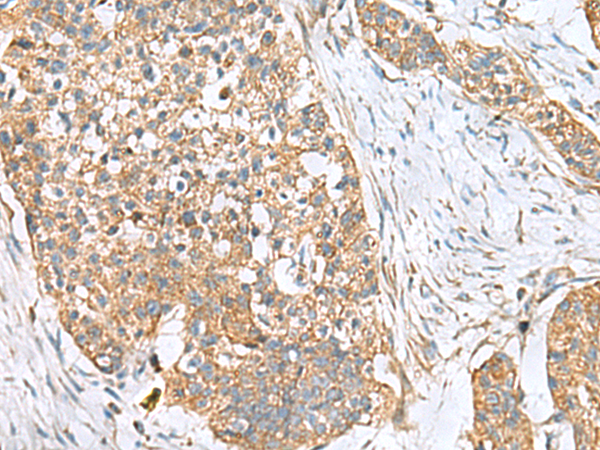

IHC (Immunohistochemistry)

(The image is immunohistochemistry of paraffin-embedded Human breast cancer tissue using AAA310795 (CEMIP Antibody) at dilution 1/120.(Original magnification: AS200))